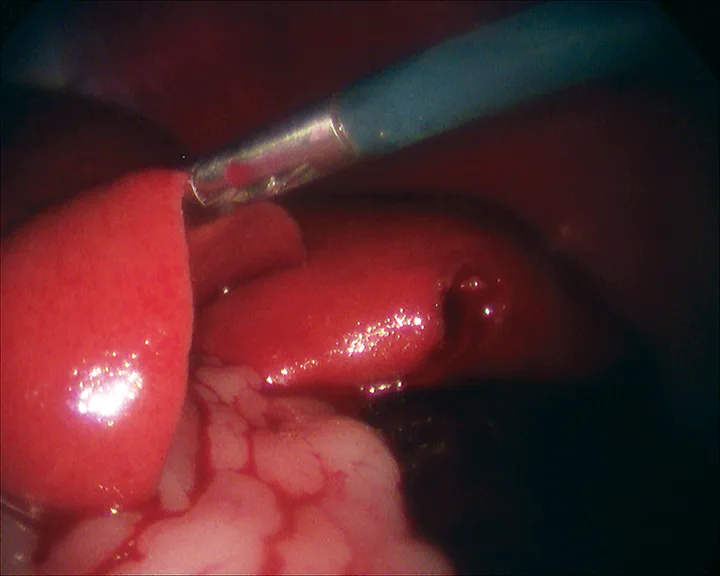

After placement of a camera and abdominal insufflation, with the patient in dorsal recumbency, the caudal abdomen is explored, and the location of the testicle is confirmed (Figure 2A). A second port is placed to allow easy access to the testicle. The testicle is grasped (Figure 2B) and exteriorized through the instrument port. The vascular pedicle and ductus deferens are double ligated extracorporeally using routine techniques, and the ligated pedicle is returned to the abdomen. If necessary, the abdomen is re-insufflated and the procedure is repeated for the contralateral testicle. The pedicle is checked for adequate hemostasis, and the port incisions are closed routinely.

FIGURE 2

Cryptorchid testicle adjacent to the small intestine in the caudal abdomen (A) and elevation of the testicle using 5-mm grasping forceps before retraction through the port and extracorporeal ligation of the vascular pedicle (B)